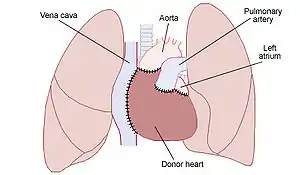

| Placement of a donor heart in an orthotopic procedure. Note how the back of the person's left atrium and great vessels are left in place. | |

Most are performed as a single heart transplant, but it may be combined with a lung, liver or kidney transplant.[1] The donor is fully heparinised before the heart is retrieved and placed in cold saline in an insulated organ transport box.[1] The more common method is bi-caval, a type of orthotopic procedure where the donor heart is placed in the same spot as the persons prior heart.[1][3] It involves joining the donor left atrium to the recipients atrial cuff, and then modelling the pulmonary artery and aorta, before releasing the cross-clamp to complete the remaining joins.[1] A heterotopic (“piggy-backed”) procedure may be done to assist left ventricular function, and involves leaving the prior heart in place while joining the donor heart to its right.[3] Heart transplantation can improve the quality and duration of life, particularly in younger recipients.[2][7] As the donor heart has lost its nerve supply, some of its functions are different.[2] It beats faster and loses the normal blood pressure variation though the day.[2]

Procedure

The orthotopic procedure is when the donor heart is placed in the same spot as the persons prior heart.[1] It can biatrial or bicaval.[1] An alternative less commonly performed method is heterotopic.[1] There is also the domino transplant.[20] A heart transplant may be combined with a lung, liver or kidney transplant.[1]